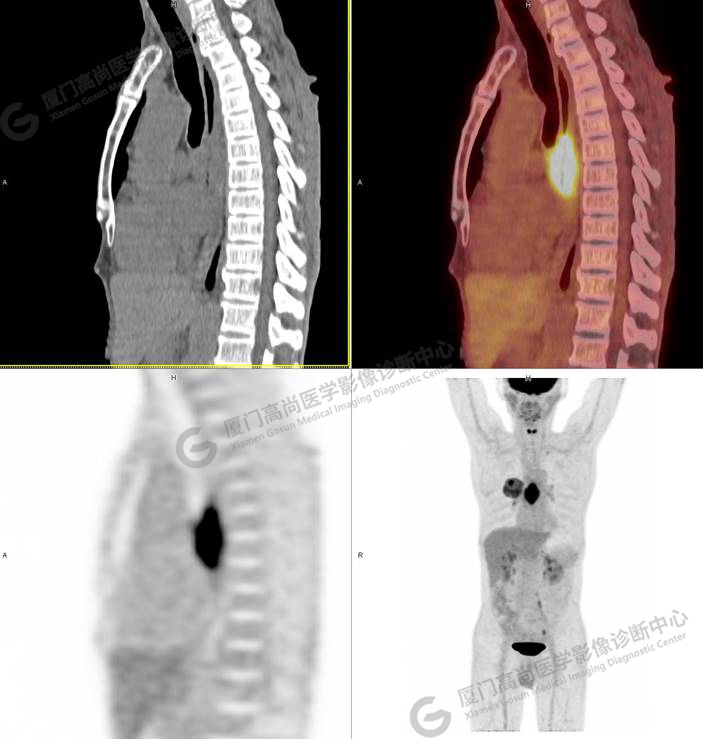

矢狀位清晰顯示,食道病灶累及長度約6cm

我中心醫(yī)師考慮張先生還有食道癌的可能性,故詢問張先生近期飲食情況,張先生表示近3個月進(jìn)食哽噎感,目前流質(zhì)飲食,加之影像學(xué)和臨床表現(xiàn)都符合食管癌!這位先生是同時罹患了兩種原發(fā)腫瘤嗎?